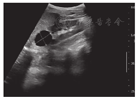

单纯肾囊肿又称为孤立性肾囊肿,好发于成人,儿童罕见[32]。该病囊壁薄而透明,常以单独疾病出现。超声检查可确诊该病,表现为一侧或两侧、单个或多个,孤立于肾皮质或髓质内边缘锐利类圆形透声区,囊腔与肾盂不相通,囊肿外肾组织正常(图7)。该病预后通常较好,一般建议随访观察,当囊肿增大、数目增多压迫肾实质或引起临床症状时可考虑手术治疗[33]。